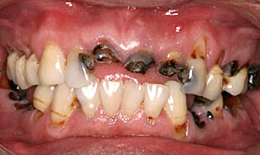

治療前

下顎

保存困難な歯を抜歯後、インプラントを4本埋め込んで、セラミックスクラウンを被せた

1. はじめに、悪い歯を抜いていきます。

2. 順番にインプラントを入れていきます。

3. 次に仮歯に変えていきます。

4. 最終と置き換えて、マウスピースを作って完成です。